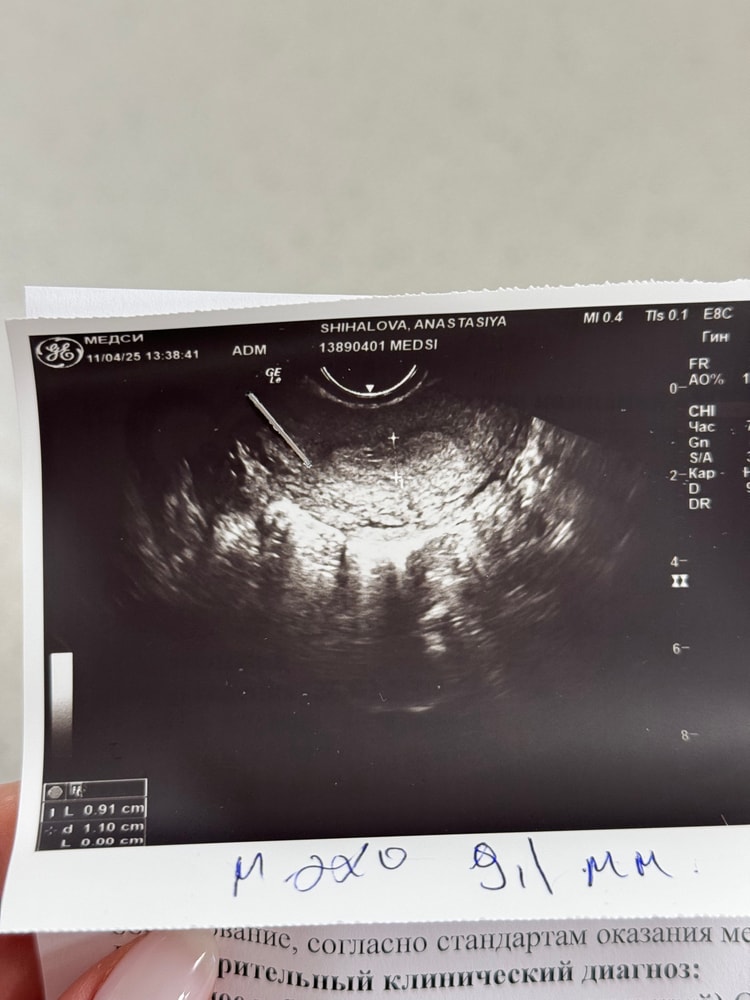

08.04. Заметили кисту в правом яичнике, а в матке образование, которое похоже на плодное тело.

11.04. Этого образования уже не было. Киста есть.